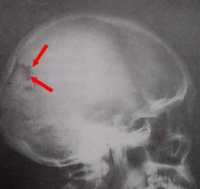

1、颅的顶面观呈卵圆形,前窄后宽,各骨之间借缝紧密相连。在额骨与

顶骨之间有冠状缝,左右顶骨之间有矢状缝,顶骨与枕骨之间有人字缝。

2、颅的侧面观颅的侧面在乳突的前上方可见外耳门,向内通外耳道。外耳门前上方的弓形骨梁称颧弓。颧弓的内上方有一浅而大的窝,称颞窝。在颞窝,额、顶、颞、蝶四骨会合处,常构成“H”形的缝,称为翼点。此处骨质较薄,内有脑膜中动脉前支通过,若发生骨折时,容易损伤该动脉,引起颅内血肿。颞窝下方的窝称颞下窝,颞下窝向内通翼腭窝。翼腭窝向下、向内侧、向前、向后及向外分别与口腔、鼻腔、眶、颅腔及颞下窝相交通,是许多血管神经的通道。